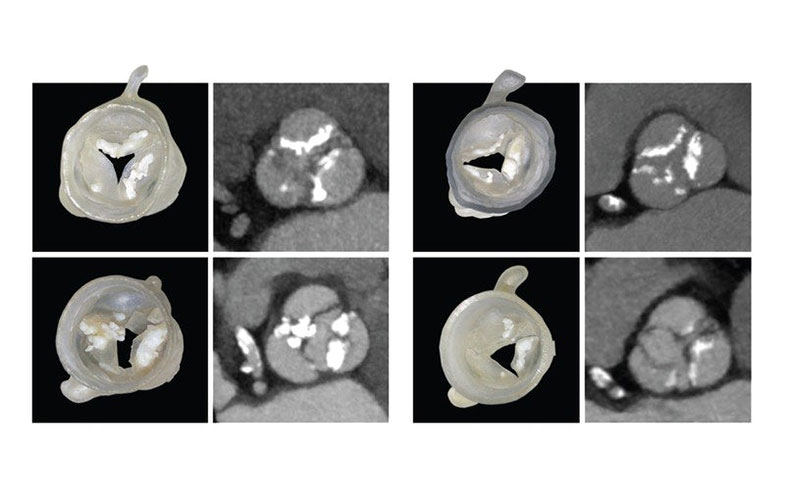

در حال حاضر دانشمندان هاروارد از ابزارهایی برخوردار هستند که میتواند انتخاب دریچههای مناسب را آسان کند. در این روش بیماران تحت یک سیتیاسکن قرار میگیرند. پزشکان نیز از تصاویر اشعه ایکس برای تولید چاپ سه بعدی قلب بیمار استفاده میکنند. این چاپ دیوارههای بیرونی آئورت و توده کلسیم را نشان میدهد.

همچنین پزشکان از یک نرمافزار جدید کامپیوتری استفاده کردند که قادر به تولید مدلهای سه بعدی از برگچهها با استفاده از مدلهای پارامتری گرفته شده از سیتیاسکن، است.